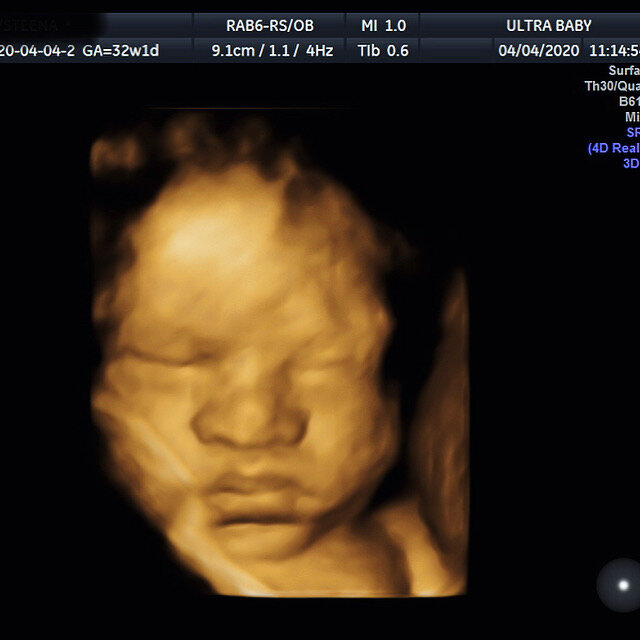

4D Examples